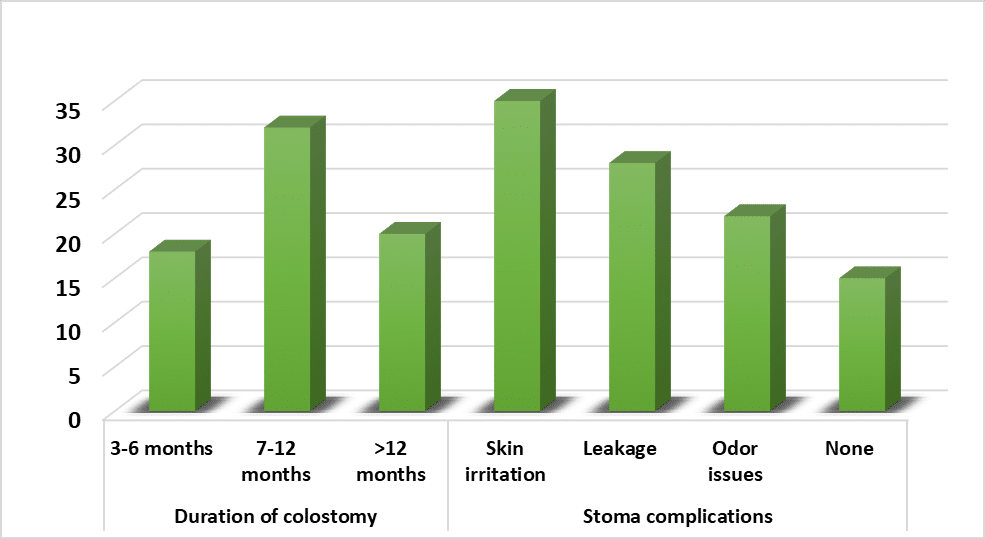

Gastroenterology | May 22, 2025

Quality of Life in Patients with Permanent Colostomy: A Cross-Sectional Study at the Tertiary Care Hospital in Swat

Background: Permanent colostomy creates major life quality changes, which damage both patients’ bodily health and their mental condition while disrupting...Read More